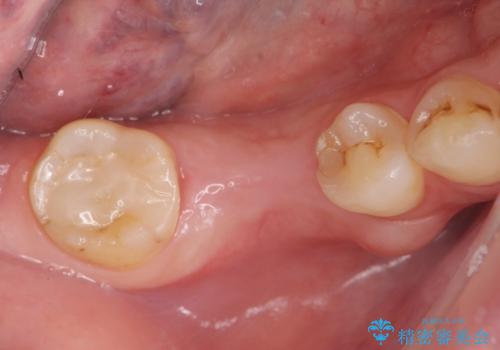

- 欠損し、放置していた奥歯に審美性に優れる入れ歯を作製したいと希望され来院されました。

ノンクラスプデンチャーは、入れ歯に通常ついている目立つ銀色のバネがないため審美性に優れる入れ歯です。

ノンクラスプデンチャーは、ブリッジのように隣りの歯を削る必要もなく、インプラントのように手術も必要ない方法です。